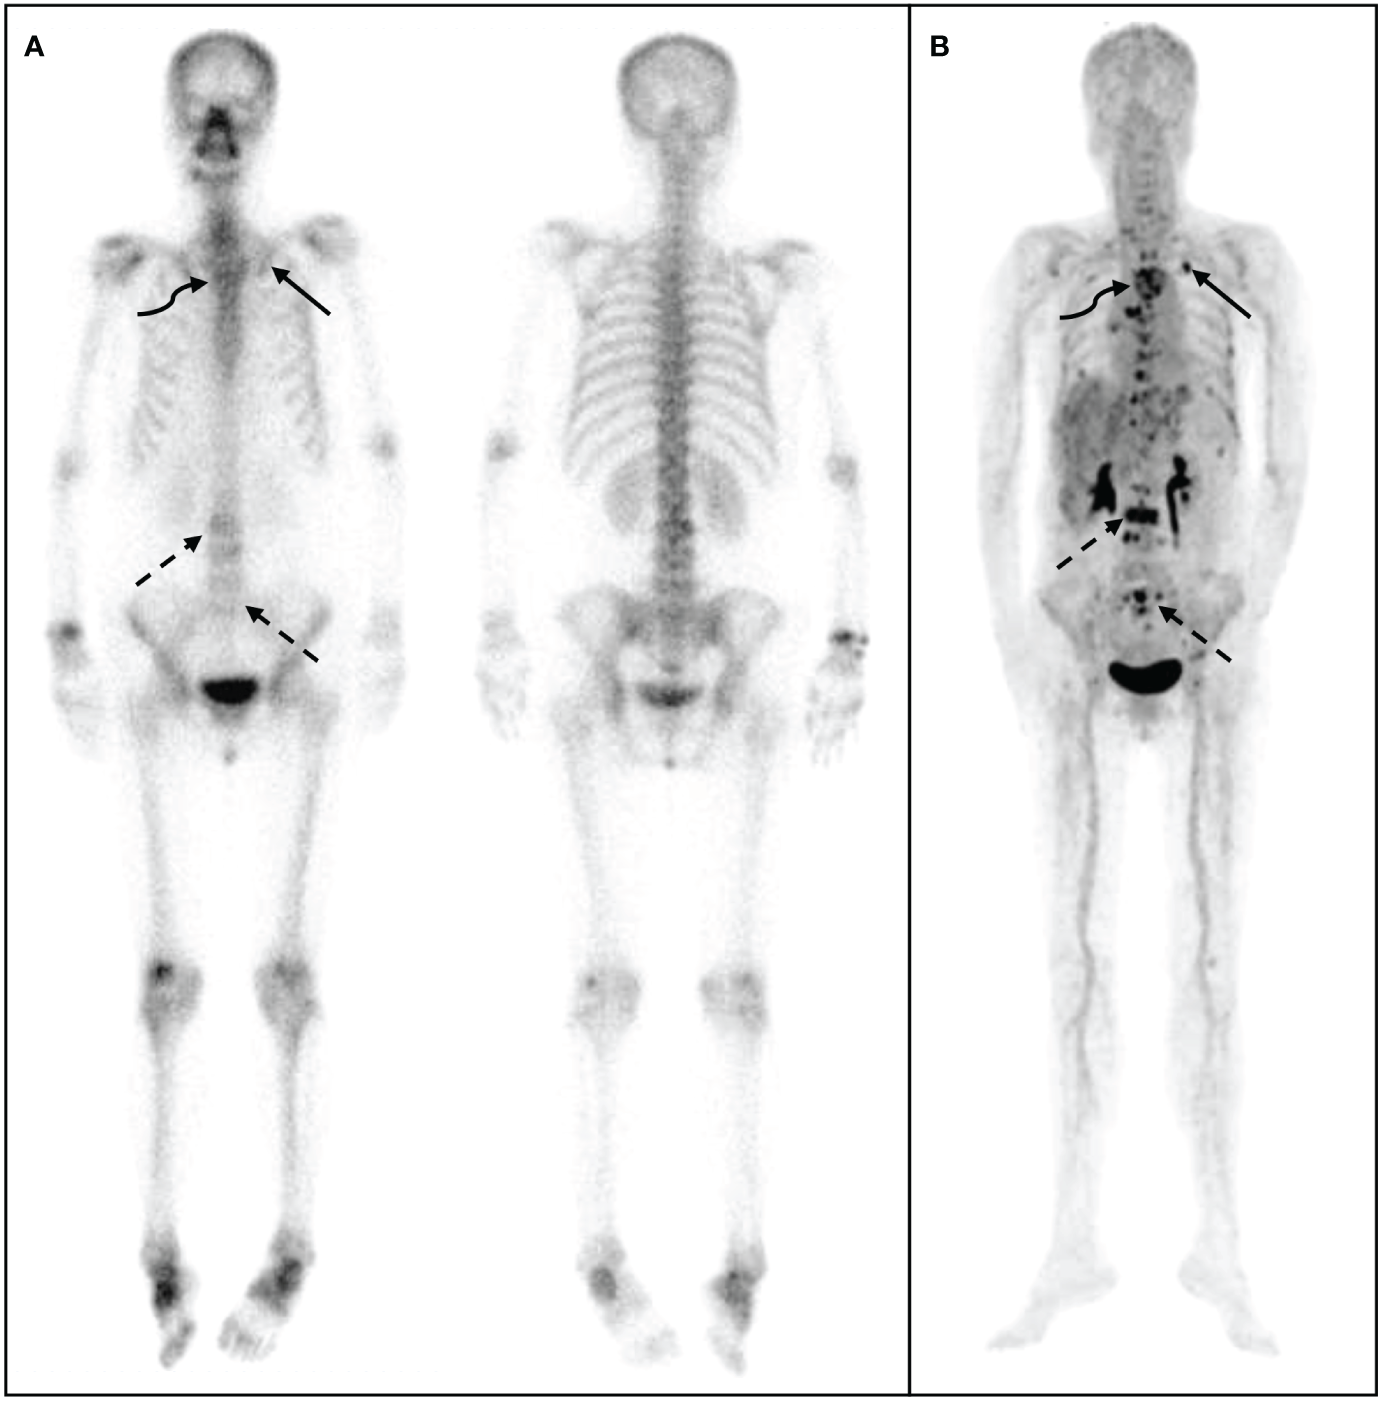

The 68Ga-DOTA-IBA PET/CT approach revealed multiple significant bone metastases in the vertebral body in cases where WBBS only showed suspicious metastases in the area; this could potentially affect the clinical treatment plans (Figure 3). Moreover, when bone metastases were detected by WBBS, 68Ga-DOTA-IBA accurately displayed multiple bone metastases with high SUVmax uptake levels, which is beneficial for radionuclide-targeted therapy and post-treatment evaluation (Figure 4). In recent years, 18F-FDG PET/CT has become a valuable technique for staging BC (14–16). However, there is ongoing debate regarding the accuracy and sensitivity of PET/CT for identifying bone metastases when compared with WBBS (17). Some scholars believe that its accuracy and sensitivity for diagnosing skull metastases are higher than those of PET/CT (18). In this study, 68Ga-DOTA-IBA PET/CT was superior to bone scans for the diagnosis of skull metastases due to the type of molecular probe used. The high uptake of FDG in brain tissues may mask skull metastases and interfere with diagnoses (19, 20), whereas 68Ga-DOTA-IBA avoids this shortcoming (Figure 4). Additionally, there is a higher uptake of 68Ga-DOTA-IBA PET/CT in non-calcified BC tissues, which may be caused by localized increase in blood pool, calcium metabolism, or interstitial volume in the breast tissue (21).

Figure 3

68Ga-DOTA- ibandronate (IBA) PET/CT performed on a 58-year-old woman with breast cancer 10 years following surgical treatment. A 99mTc-MDP bone scan (A) shows no significant increase in bone metabolism, whereas a 68Ga-DOTA-IBA PET/CT shows (B) multiple bone metastases throughout the body and significantly increased bone metabolism in the ribs (straight arrow), spine (dotted arrow), and sternum (curved arrow).

Figure 4

68Ga-DOTA- ibandronate (IBA) PET/CT performed on a 48-year-old woman with invasive cancer 4 years following surgical treatment for BC. A 99mTc-MDP bone scan (A) shows multiple bone metastases in sites such as the vertebral body, ribs, ilium, and humerus. A 68Ga-DOTA-IBA PET/CT (B) reveals more vertebral (straight arrow) and rib (curved arrow) metastases, particularly in the pelvis (dotted arrow).